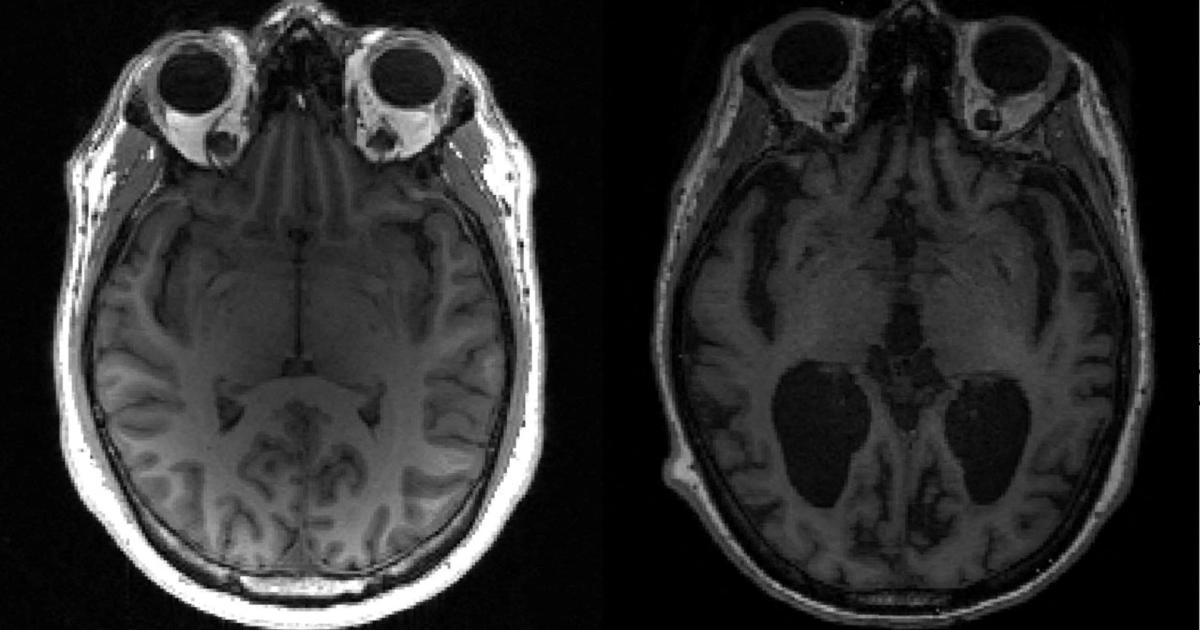

Μέχρι σήμερα, οι πιο αξιόπιστες μέθοδοι για την ανίχνευση της νόσου Αλτσχάιμερ απαιτούσαν επεμβατικές και δαπανηρές τεχνικές, όπως η λήψη εγκεφαλονωτιαίου υγρού. Οι επιστήμονες διερευνούν εδώ και χρόνια τη δυνατότητα εντοπισμού της νόσου, η οποία προσβάλλει 800.000 άτομα μόνο στην Ισπανία, με μια εξέταση αίματος, λόγω των δυνατοτήτων της να βελτιώσει την έγκαιρη διάγνωση.

Σύμφωνα με τον Ελόι Ροντρίγκεζ, επικεφαλής του Τμήματος Νευρολογίας στο Πανεπιστημιακό Νοσοκομείο Marqués de Valdecilla-IDIVAL, η πρόοδος αυτή "θα συμβάλει στον εκδημοκρατισμό της βιολογικής διάγνωσης ακριβείας της νόσου Αλτσχάιμερ", η οποία θα αποφύγει σε πολλές περιπτώσεις πιο επεμβατικές ή δυσπρόσιτες τεχνικές, όπως η οσφυονωτιαία παρακέντηση ή η PET αμυλοειδούς, μια πολύ ακριβή απεικονιστική εξέταση. Ο εμπειρογνώμονας είναι αισιόδοξος για τη δυνατότητα επέκτασης της χρήσης αυτού του δείκτη "από εξειδικευμένες σε λιγότερο εξειδικευμένες επισκέψεις".